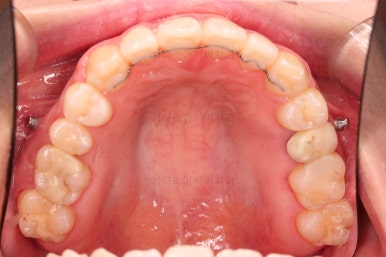

부산치아교정잘하는곳 키다리아저씨치과에서 치료를 종료했을 때의 사진입니다.

위아랫니가 가지런해졌고요.

다시 틀어지지 말라고 적절한 유지장치를 구성합니다.

보철 치아의 위치/크기로 인해 100% 중앙선은 맞기 힘드나 가장 잘 맞추어 놨고, 앞니의 각도도 매우 좋아졌습니다.

아래 앞니도 단순히 머리 부분만 뒤로 눕힌 것이 아니라 뿌리까지 뒤로 당겨왔고요.

교합, 가지런함, 앞니 각도 모두 좋아졌습니다.